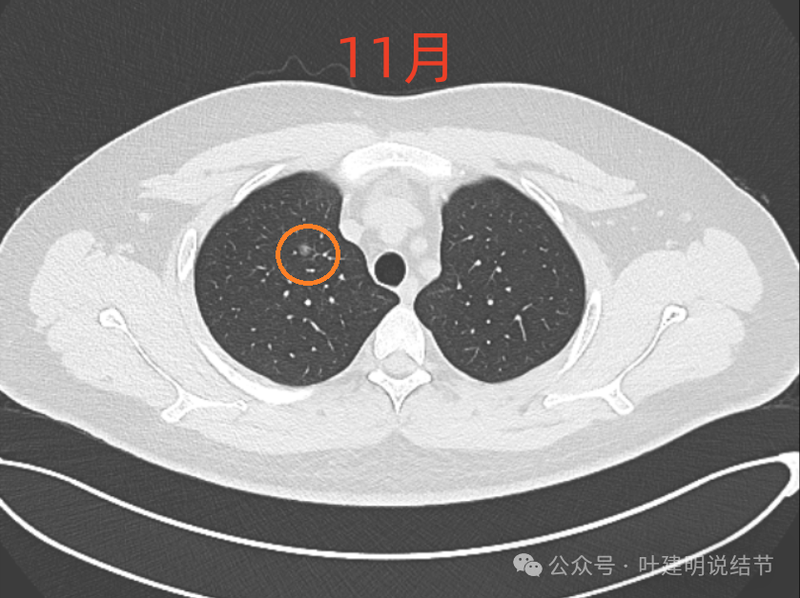

2024年8月5日年度体检薄层CT显示多发结节,2024.11.14复查发现其中一个混合磨玻璃结节新见实性密度影,未诉明显不适,为进一步治疗,特来问诊。

右肺尖磨玻璃结节,整体轮廓与边界清,有微小血管进入与穿行,但肿瘤本向说不上实性密度。

8月时似乎略模糊点,但显著的变化显然仍是说不上的。风险并不能算高,当然东西是肿瘤范畴的,原位癌或不典型增生均可能。

现在的人工智能辅助诊断系统太过敏感,非常微小的结节都给你找出来,但是对于临床来说并没有多大意义。当结节才几个毫米的时候,既没有办法明确到底是什么,也没有必要明确到底是什么,按照中华医学会肺癌诊疗指南,8毫米以下纯磨玻璃结节或5毫米以下实性结节(包括混合密度结节实性成分不足5毫米)也就是年度复查就可以。所以其实并不一定要在意到底有多少处结节,或者要考虑是什么。主要就关注最主要的病灶,如果主病灶仍没有风险可以年度体检复查,那就可以随访,不能也不必有过大的思想顾虑。我看了你的CT,目前这些结节均风险小,其中右侧桔色框起来的是所谓主病灶,仍是纯磨密度,又还小,考虑不典型增生可能性较大;左下桔色的也是磨玻璃密度,但轮廓不如右上这处清楚,若确实肿瘤范畴,也是原位癌或不典型增生可能性大,但也有少许慢性炎伴肺泡上皮增生或纤维增生的可能性;中叶绿色的密度过高,更符合良性些;右下黄色的过小,11月份的像磨玻璃密度,边界较清,但对比8月时的,此灶不太明显,当然本身过小,也可能没有扫到最明显层面,不过总归风险小,能观察随访(左下的也8月时更显淡和不明显点)。总体上,这几处病灶都是风险还低,可以继续半年到一年复查随访,真若有明显进展并具有一定的风险再来干预处理不影响预后。本身年纪轻,又是多发结节,目前的病灶又都风险低,可以过于积极赶紧处理。意见供参考!